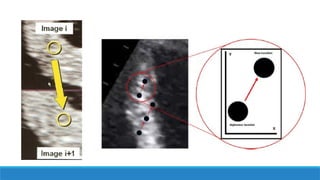

♣ Le strain myocardique ou 2D Strain ou speckle tracking = raccourcissement d’un segment

myocardique par rapport à son état initial dans les différents axes de l’espace (longitudinal, radial

et circonférentiel) évalué par le suivi du déplacement spatial « tracking » de marqueurs

acoustiques naturels « speckles » au sein au sein de l’image échographique 2D du tissu

myocardique

♣ Il est exprimé en pourcentage de modification par rapport à la dimension originelle.